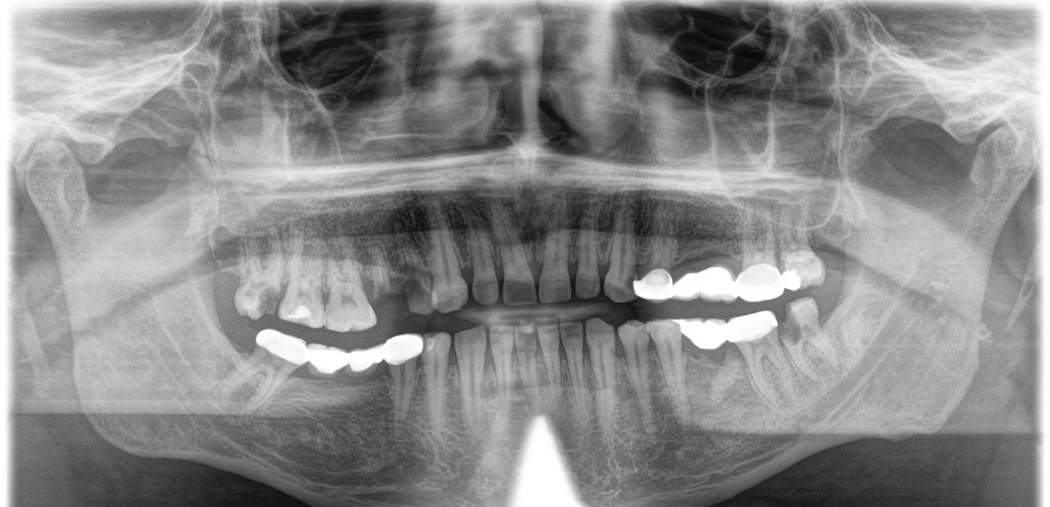

Röntgen görüntüsü, aşağıdaki bulgulara sahip bir hastayı (erkek, 59 yaşında) göstermektedir: 47, 36 Kapsamlı periapikal osteitis ve 14 apikal osteitis. 14-16 endodontik restorasyon, 22 aşırı dolu kök kanalı, 45 yetersiz kök dolgusu, 18 derin çürükler, 45 dikey ve yatay kemik kaybı. 1. Ameliyattan önce daha fazla açıklama yapabilmek için, Orthophos SL kullanarak 8x8 cm 3D görüntü ürettik.